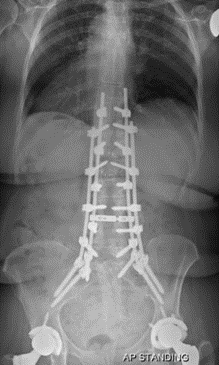

2.减少融合节段,尽量保留远端活动节段以降低近端应力

图24 左:长节段固定至髂骨;右:长节段固定